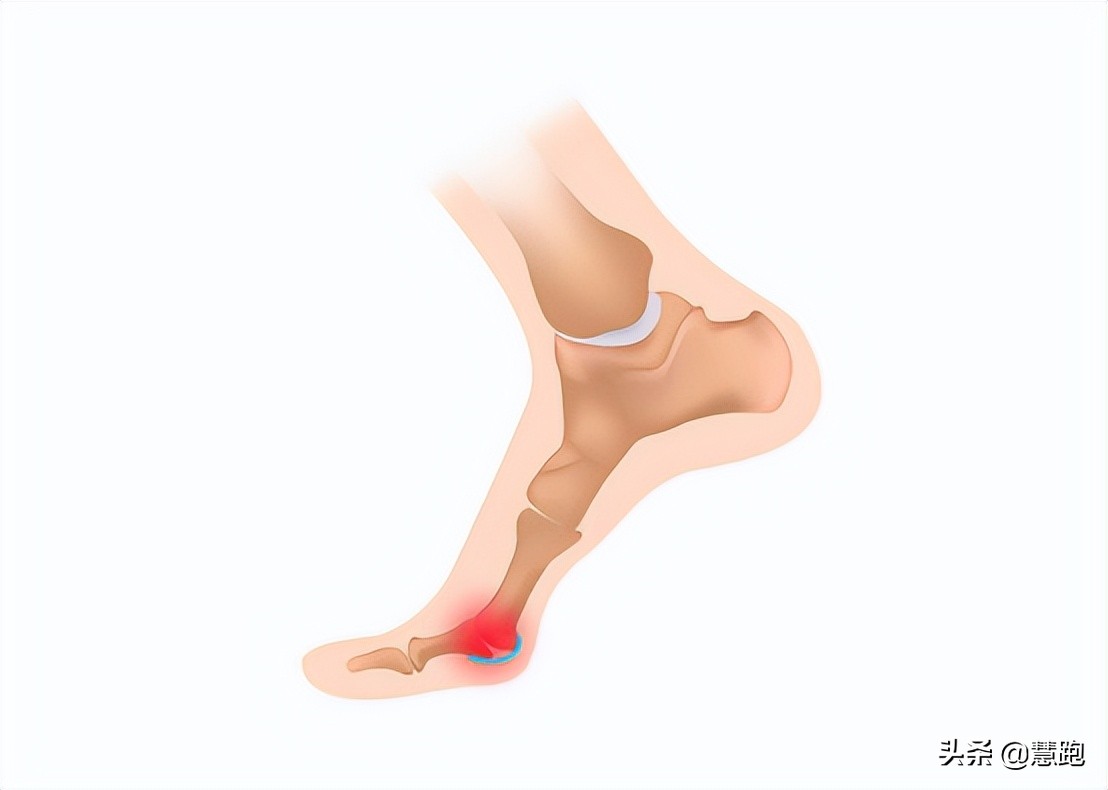

足底筋膜炎的典型表现

患有足底筋膜炎当然会感觉足底疼痛,疼痛的具体特点包括以下几方面:

● 最典型症状:早晨醒后下床,脚落地时,足跟部疼痛最为明显,走动一会儿后疼痛会有所缓解;

● 典型症状:休息一段时间比如看电影、久坐工作后,或者足部在不负重一段时间后,站起行走的前几步出现隐隐作痛;

● 疼痛的具体位置实在在足跟靠内侧处,这里恰恰是足底筋膜从足跟发出的起点处,偶尔也有患者会反映疼痛在足底中部;

● 患者自己感觉在充分活动后如行走或跑步后,足跟部疼痛减轻,但是在长距离跑步后程,可能再次出现疼痛甚至被迫停下脚步,还有患者反映晚间足跟部疼痛会加重;

● 足底筋膜炎女性更为多见

足跟特定部位按压疼痛和晨起下床足跟痛,是判断足底筋膜炎的重要依据。

此外,跑者可以通过一个被称为“卷扬机试验”的测试来进行自我诊断。采用坐位,握住大脚趾,将大脚趾用力背伸,如果诱发疼痛,则提示是足底筋膜炎。

有跑者到医院检查,拍片后显示有跟骨骨刺(专业术语称为跟骨骨赘),大惊失色,会认为足底长出骨刺自然戳着疼。其实,骨刺不是导致疼痛的主要原因,骨刺刺激了足底筋膜才是产生疼痛的主要原因,足底筋膜炎治好了,自然疼痛也就消失了,所以对于跟骨骨刺不必过度担心。